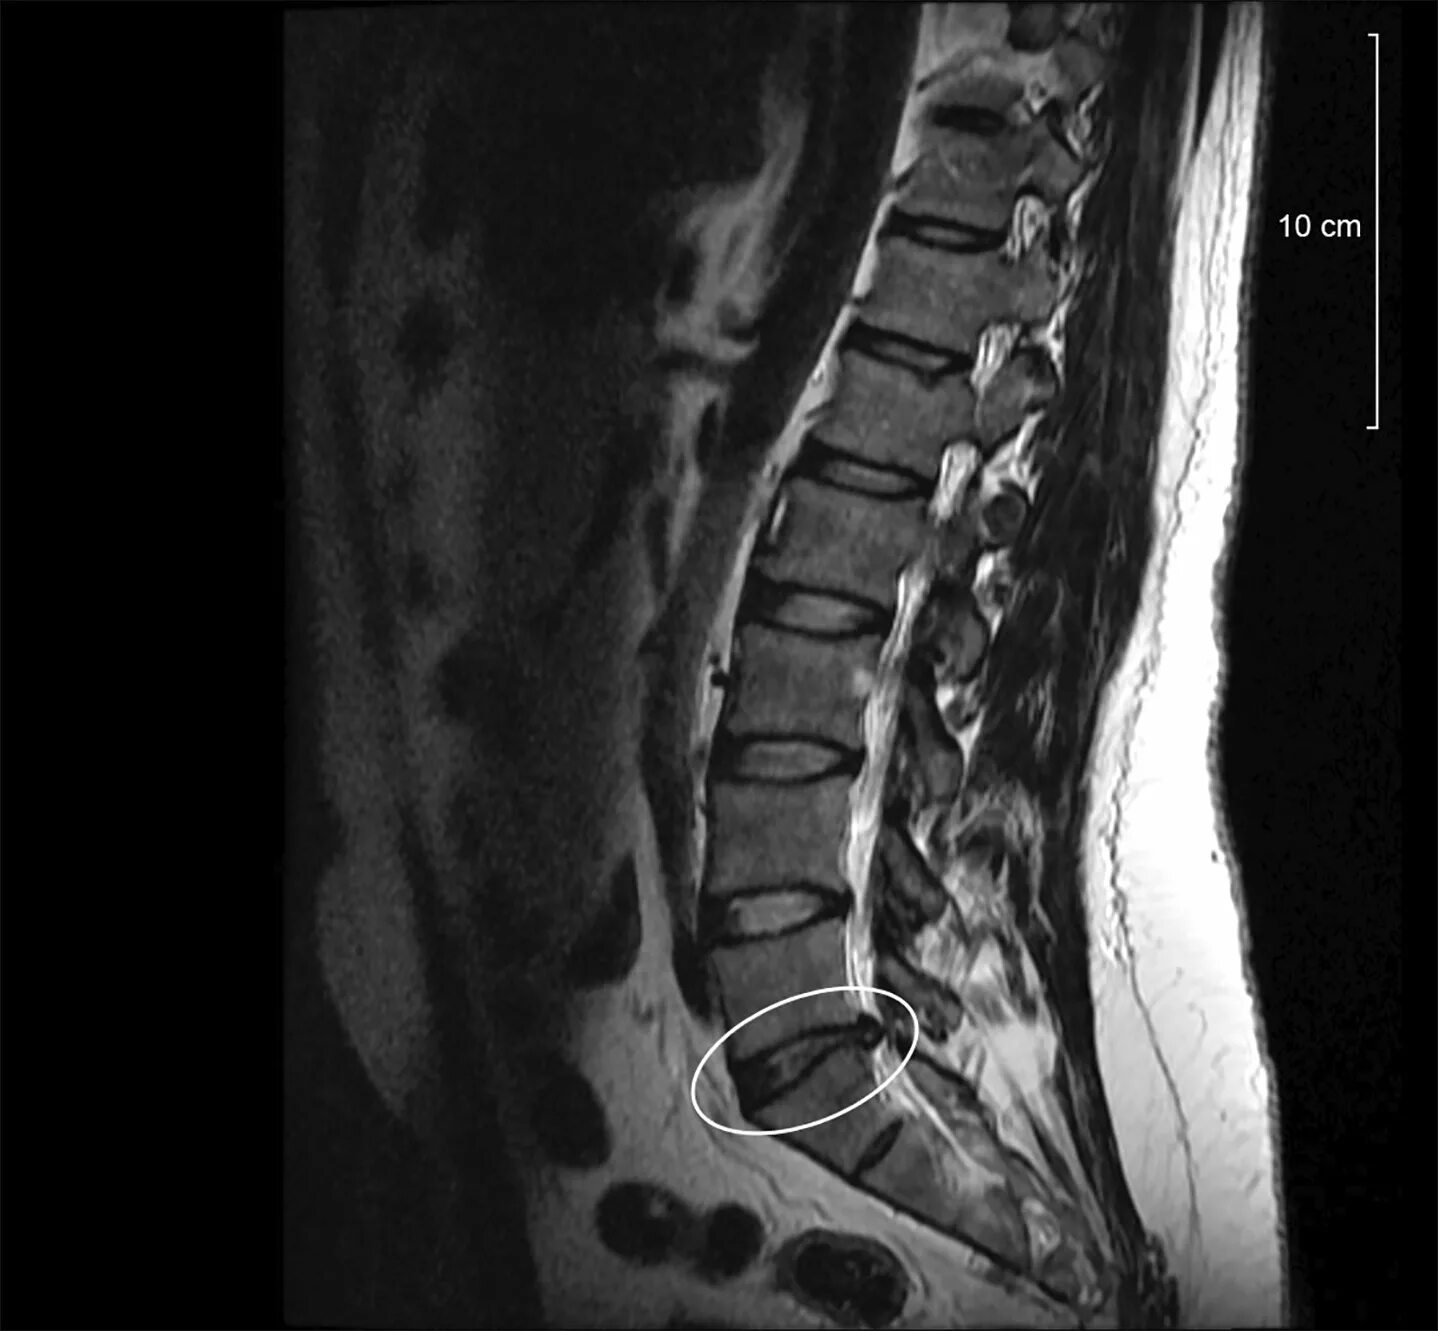

Грыжа диска 0.5 см